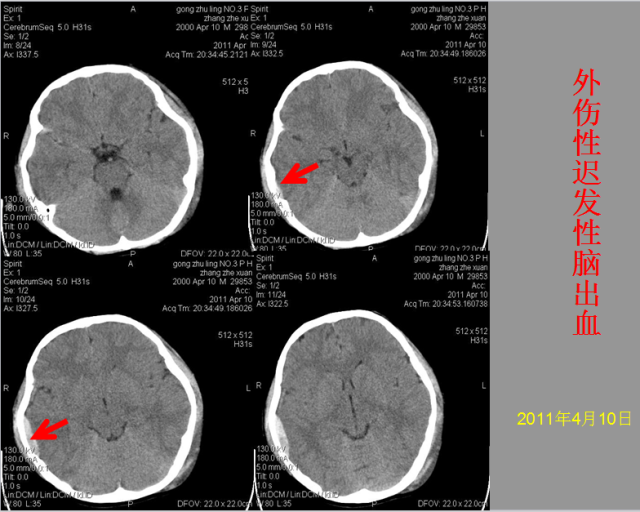

急性颅脑损伤篇

03